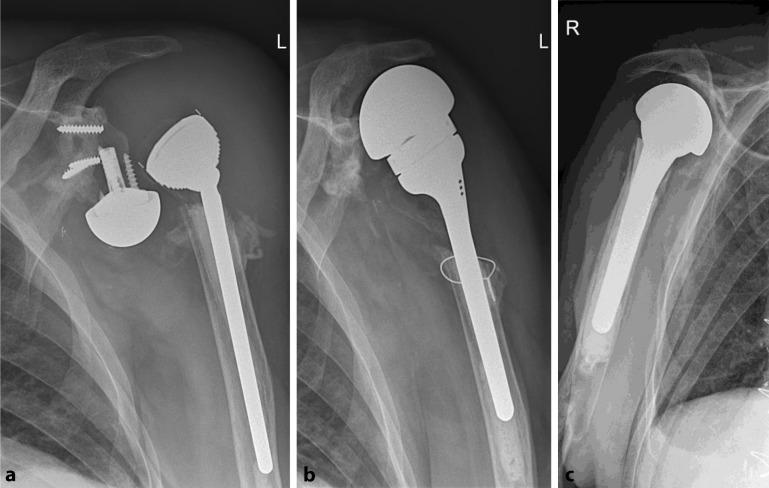

Indications for implantation of a megahead prosthesis were loosening RSA ( = 5), infection ( = 4), dislocation ( = 1) and nerve irritation ( = 1). Improvement of range of motion was observed. Anterosuperior migration of the prosthesis was noted in 2 patients. Another 2 patients were ultimately revised to RSA. Seven permanent spacers were implanted for infection, of which 2 remain in place till today. The other 5 were revised to RSA. Of the 5 patients treated with RA, 3 were revised further on to RSA, resulting in pain relief and regain of function.

植入大头假体的指征包括RSA松动(n = 5)、感染(n = 4)、脱位(n = 1)和神经刺激(n = 1)。观察到活动范围有所改善。2例患者出现假体前上移位。另外2例患者最终翻修至RSA。因感染植入了7个永久性间隔物,其中2个至今仍在位。另外5个翻修至RSA。在接受RA治疗的5例患者中,3例进一步翻修至RSA,疼痛缓解且功能恢复。